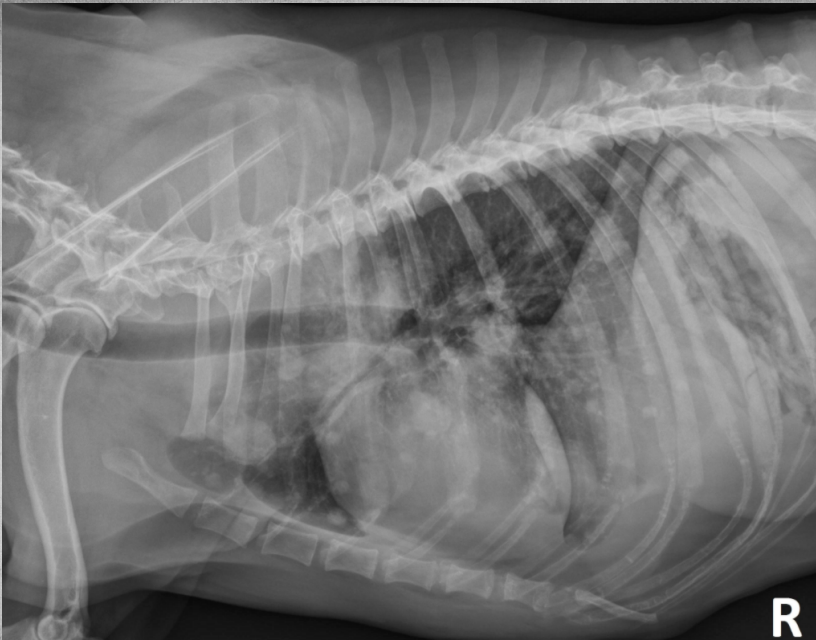

● 12 yo dog

● Coughing for 2 months

alveolar pattern caudodorsally (black tree visible)

fat in ventral thorax

cardiac silhouette lifted and rounded, maybe free fluid

on VD: mass effect